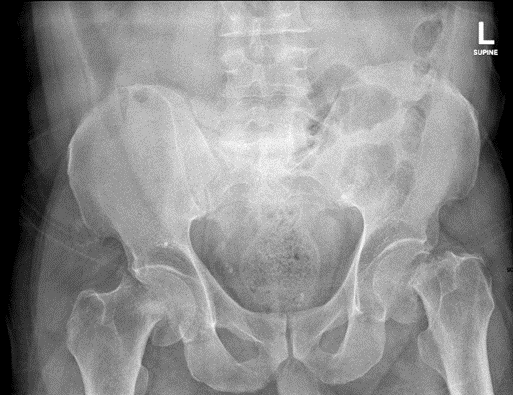

The patient tolerated both procedures well and was extubated postoperatively without complications. He was transferred to the recovery room in stable condition. post-operative radiographs confirmed proper implant positioning (Figure 2). He was managed with pain control, deep vein thrombosis (DVT) prophylaxis, and nutritional optimization, including a potassium-restricted diet. Endocrinology consultation post-operatively revealed severe osteoporosis, and the patient was initiated on romosozumab alongside high-dose vitamin D.

Figure 2: Postoperative X-ray showing bilateral hip hemiarthroplasty with aligned implants.